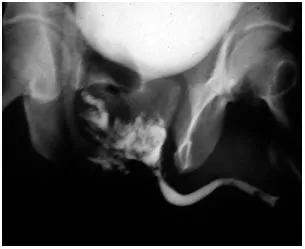

- Crucial First Step: ALWAYS perform a retrograde urethrogram (RUG) in stable patients before any catheterization attempt.

- Initial Diversion: A suprapubic tube is placed for urinary drainage. This is done immediately in unstable patients or after RUG confirms a tear.

⭐ High-Yield: Blind Foley catheter placement is contraindicated. It can convert a partial tear into a complete disruption, complicating future repair.

- Posterior urethral injury: Suspect with pelvic fracture, blood at meatus, and a high-riding prostate.

- First step for suspected urethral injury is a retrograde urethrogram (RUG).

- AVOID blind Foley catheterization in urethral trauma; perform suprapubic cystostomy.